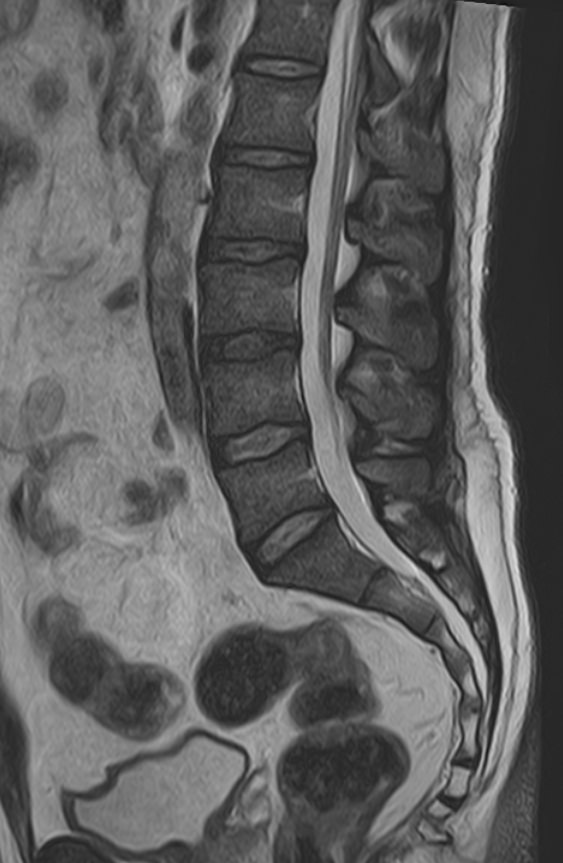

В нашей клинике мы проводим комплексное исследование, включающее МРТ головного мозга и всех отделов позвоночника. Методика комплексного обследования применяется при наличии у пациента сочетанных поражений головного мозга, спинного мозга и позвоночного столба.

При подозрении на распространенный процесс с поражением различных уровней позвоночника целесообразно проведение МРТ для диагностики дегенеративно-дистрофических заболеваний, травматических, воспалительных изменений, а также опухолевых процессов позвоночника. Метод позволяет оценить состояние структур позвонков, позвоночного канала с расположенным в нем спинным мозгом и окружающих мягких тканей, кроме того, является основным способом диагностики демиелинизирующих заболеваний спинного мозга.

Исследование проводится на современном томографе TOSHIBA VANTAGE TITAN 1,5 Тесла. За счет высокой индукции магнитного поля аппарат обладает  высокой разрешающей способностью, что позволяет проводить точную диагностику заболеваний центральной нервной системы и позвоночника.